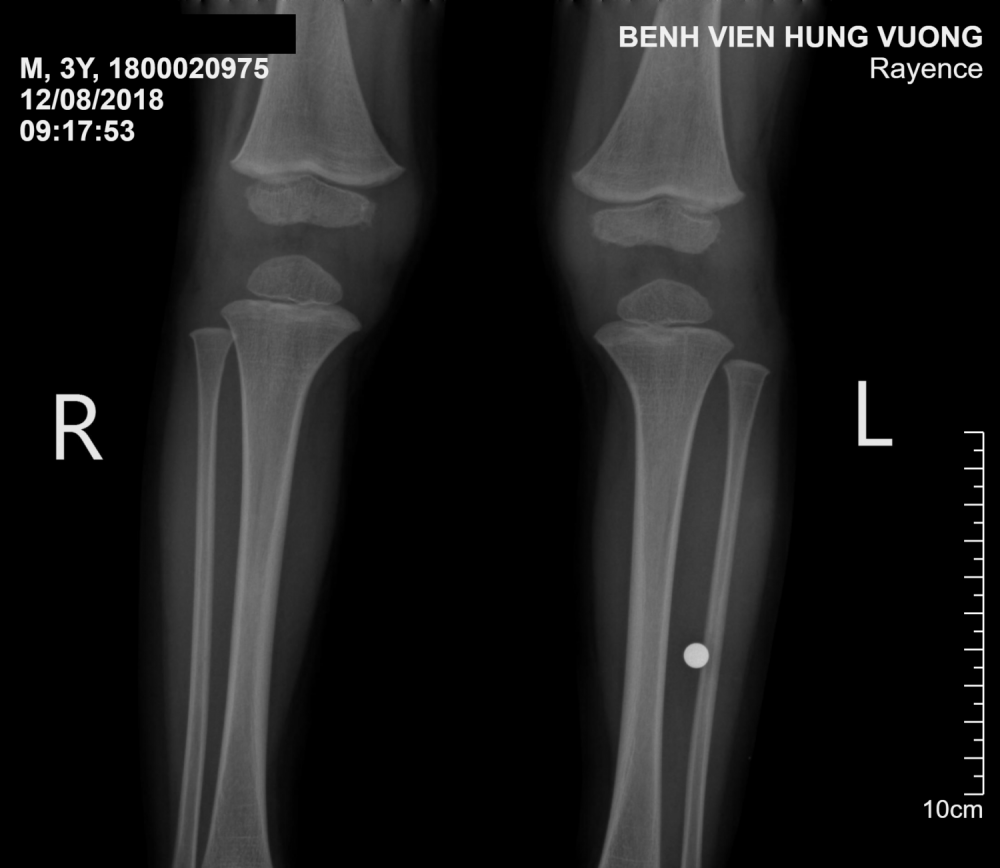

Hình ảnh chụp X - Quang phát hiện có dị vật hình tròn nằm trong sâu cẳng chân bệnh nhân

Qua thăm khám, sàng lọc ban đầu và dựa vào hình ảnh của phim X - Quang, các bác sĩ của Bệnh viện Đa khoa Hùng Vương phát hiện trong cẳng chân trái bệnh nhi trên có hình ảnh dị vật hình tròn, cần phải xử lý gấp.

Trong quá trình phẫu thuật, các bác sĩ đã gắp ra khỏi cẳng chân bệnh nhi trên 1 dị vật hình tròn, giống viên bi đồ chơi dành cho trẻ em có đường kính 5mm.